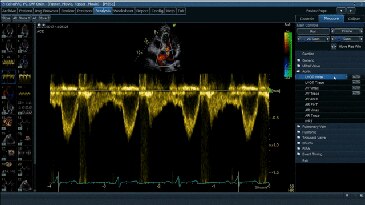

Cardiac Auto Doppler